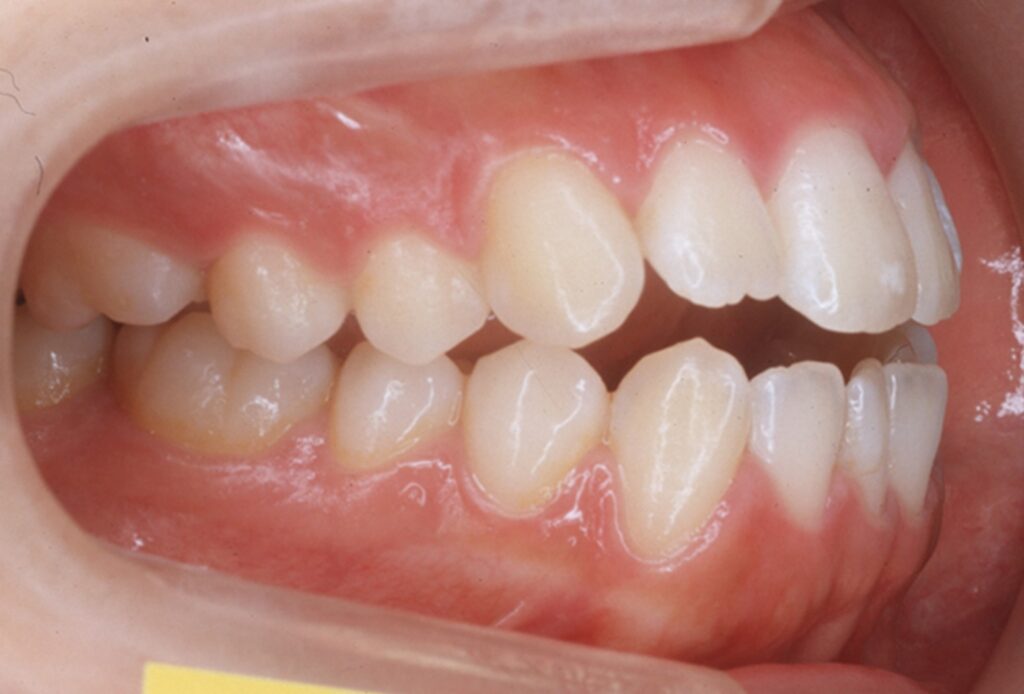

虫歯になりやすい歯並びの他に、虫歯になりやすい噛み合わせということがあります。

虫歯になりやすい噛み合わせの例を説明していきましょう。

「反対咬合(下あご前突)」こちらは受け口と言われるかもしれませんが、下の歯が前に出てしまっている人です。

写真を見ると分かりやすいかもしれませんね。

あともう一つ。

「開咬(かいこう)」といって、前歯が噛めない人がいます。

噛んでもらうと、奥歯だけ噛んで前歯が当たらない人です。

開咬の人は一見すると、歯の並びは綺麗に並んでいるため、自分が歯並びが悪い(噛み合わせが悪い)という事に気づいていません。開咬の人は、麺類などを前歯で噛み切ることができません。しかし今まで指摘されていなければ、そういうものと生活しているので、正しい噛み合わせの人は前歯が食べ物が噛み切れることを説明すると驚かれます。

この「反対咬合」と「開咬」の方に共通していることは、「奥歯しか噛めない」という事です。通常、歯は上下・全体で噛み合って負担を分散するのですが、前歯が噛めない人は奥歯に過重負担が起こります。それにより、奥歯に亀裂やヒビが入り、その隙間から虫歯菌が侵入することが多くあります。これが他の人より虫歯になりやすい原因です。